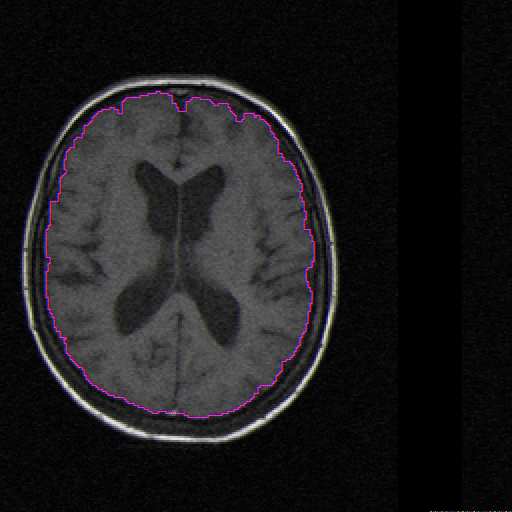

Progressive Livewire is a tool for image sequence segmentation. Our specific application was in segmenting the brain from MRI slice images. The advantage of our method is its high level of automation. The user needs only segment the first image, and segmentation of the rest of the image is automatically completed. Additionally, segmenting the first image of the sequence is aided by an optimum boundary finding routine based on the livewire algorithm [1].

The Java applet below demonstrates the user interaction of the algorithm. To use it, click "Train" (or press "t") and paint (by dragging the mouse) a small portion of the correct boundary. Note that any boundary can be used, but the surface of the brain is typically the most dramatic. After painting a boundary region, a cost image will appear to the right of the MRI. The cost image is a representation of the actual cost function being used by the segmentation algorithm. Higher pixel intensities correspond to lower costs, so a good cost image will show the desired boundary in white and other image features in gray and black.

Once the alogrithm has been trained, simply click a point on the boundary and move the mouse. An optimal path connecting the initial point and the current location of the mouse pointer will be shown. As the mouse is moved, the boundary is updated. When a good partial boundary has been found, clicking the mouse will make this part of the boundary permanent and use the end of this boundary as the starting point for a new boundary segment. At any time choosing "Train" again will retrain the algorithm on the current boundary to refine the cost function.

After choosing a few points and coming back to the starting point, clicking "Close Contour" (or pressing "c") will complete the boundary by connecting it to the starting point again. Now a complete pixel-resolution region has been segmented. In the complete program, this stage would be followed by propogating the contour to more images until segmentation of the complete image sequence was finished.